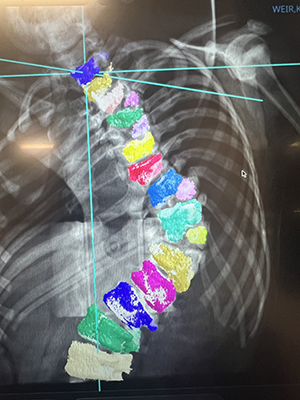

While every patient and treatment is unique, Borden said it’s even more essential for congenital scoliosis patients. It requires a customized approach for every level of the spine. In Kai’s case, Borden utilized a preoperative MRI and CT scan, from which a 3D print model of Kai’s spine was produced.

“The model allowed us to hold the spine in our hands and plan cuts in the bone needed to straighten the spine,” Borden said. “We could determine exactly where we wanted to remove bone to get the best correction for him.”